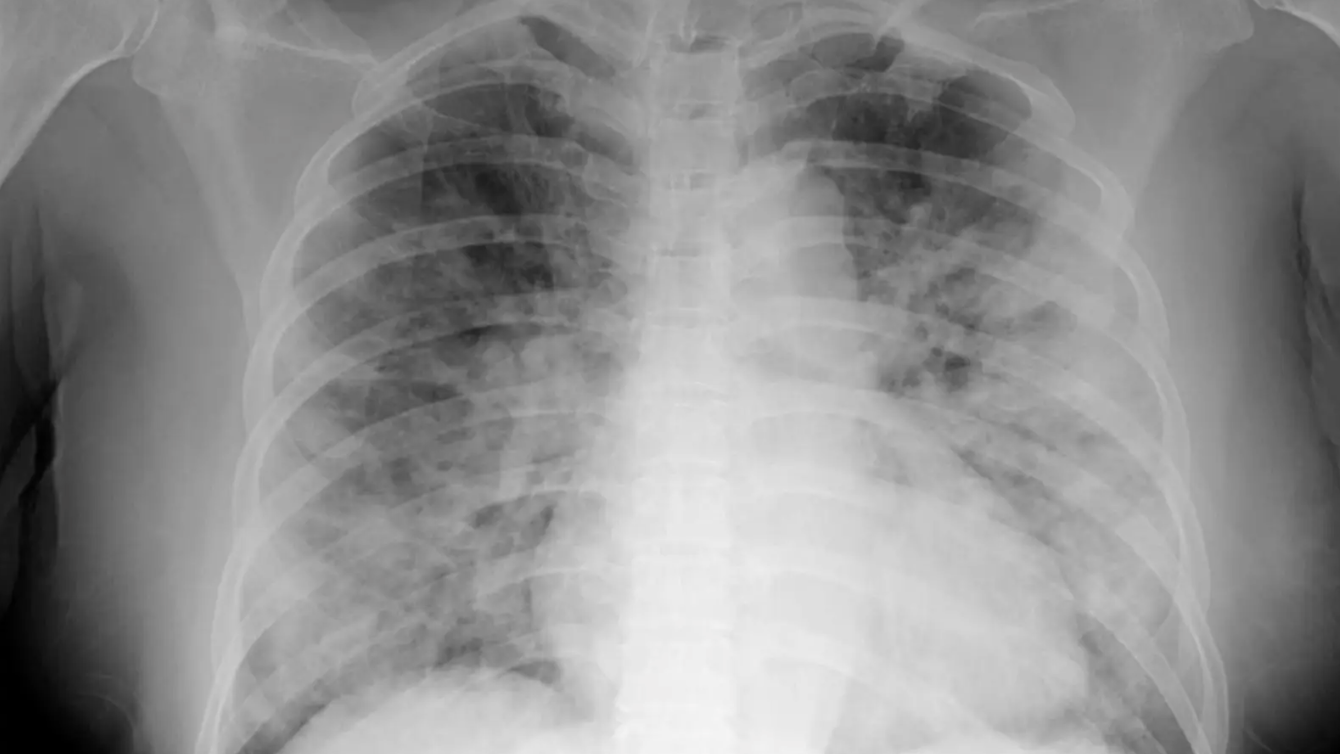

From stock.adobe.com

chest xray image of covid 19 pneumonia patient show consolidation How Does Chest Feel During Covid It can feel like you’re breathing through a straw. On a chest ct, they may see. Once in the chest, the virus begins to impact a person's airways — causing. And the vast majority of people will be managing their symptoms. shortness of breath, persistent cough and fatigue are common covid signs and symptoms. your chest may feel. How Does Chest Feel During Covid.